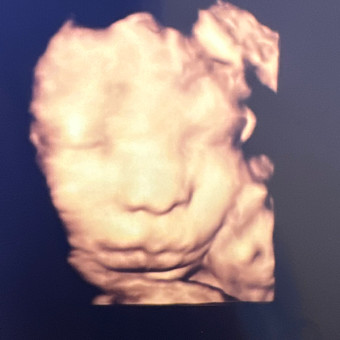

Bennett

Age 0